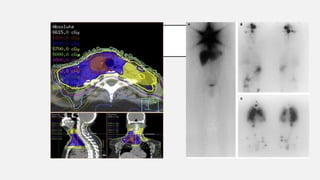

SPECT PET/CT

DIAGNÓSTICO

CT PET PET/CT